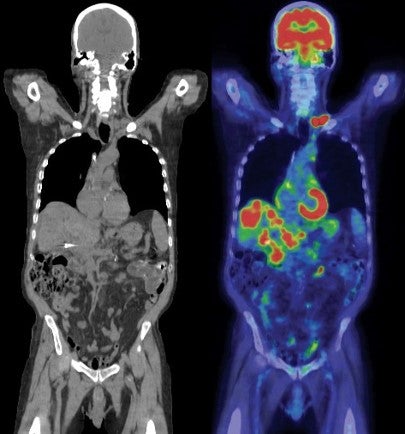

Trusted Diagnostics, Advanced Imaging

At SGH Radiological Sciences, our team uses advanced imaging and minimally invasive techniques to help diagnose and treat a wide range of conditions. As a teaching and research centre, we are also constantly improving how we deliver safer, faster, and more accurate results.